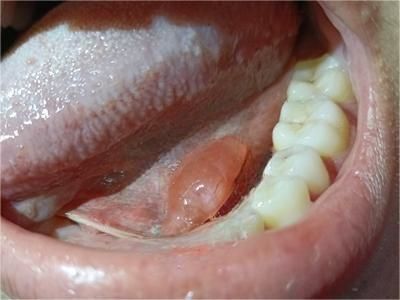

舌下腺囊肿下颌一侧长了大疙瘩图

舌下腺囊肿患者下颌区会出现一凸起的半球形肿物,外观形似大疙瘩,口底囊肿表现并不明显,触之柔软,与皮肤无粘连,可压缩,患者有明显的异物感。